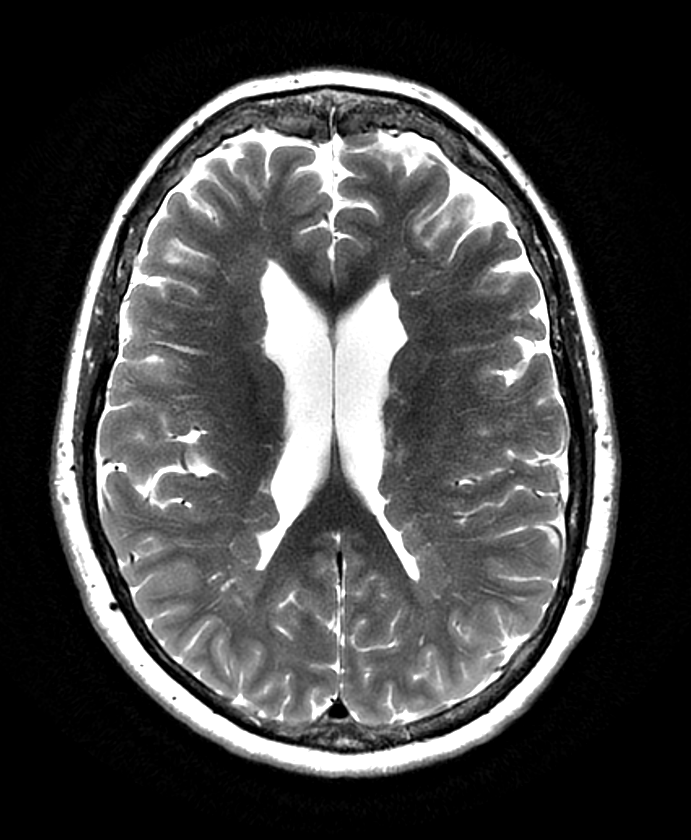

- MRI findings:

- T1-weighted: Isointense to normal grey matter

- T2-weighted: Isointense to normal grey matter

- FLAIR: Isointense to normal grey matter

- Types of heterotopia:

- Subependymal (periventricular nodular heterotopia)

- Subcortical

- Band heterotopia (double cortex syndrome)

- Associated findings:

- Corpus callosum abnormalities

- Cortical malformations (e.g., polymicrogyria)

- Cerebellar anomalies